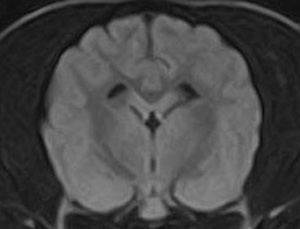

市内の先生からけいれん発作が出るとのことでMRI検査のご依頼がありました。検査では脳に構造上の異常を認めず、脳脊髄液検査も問題なく、特発性てんかんとの診断でご紹介もとの病院様での治療となりました。